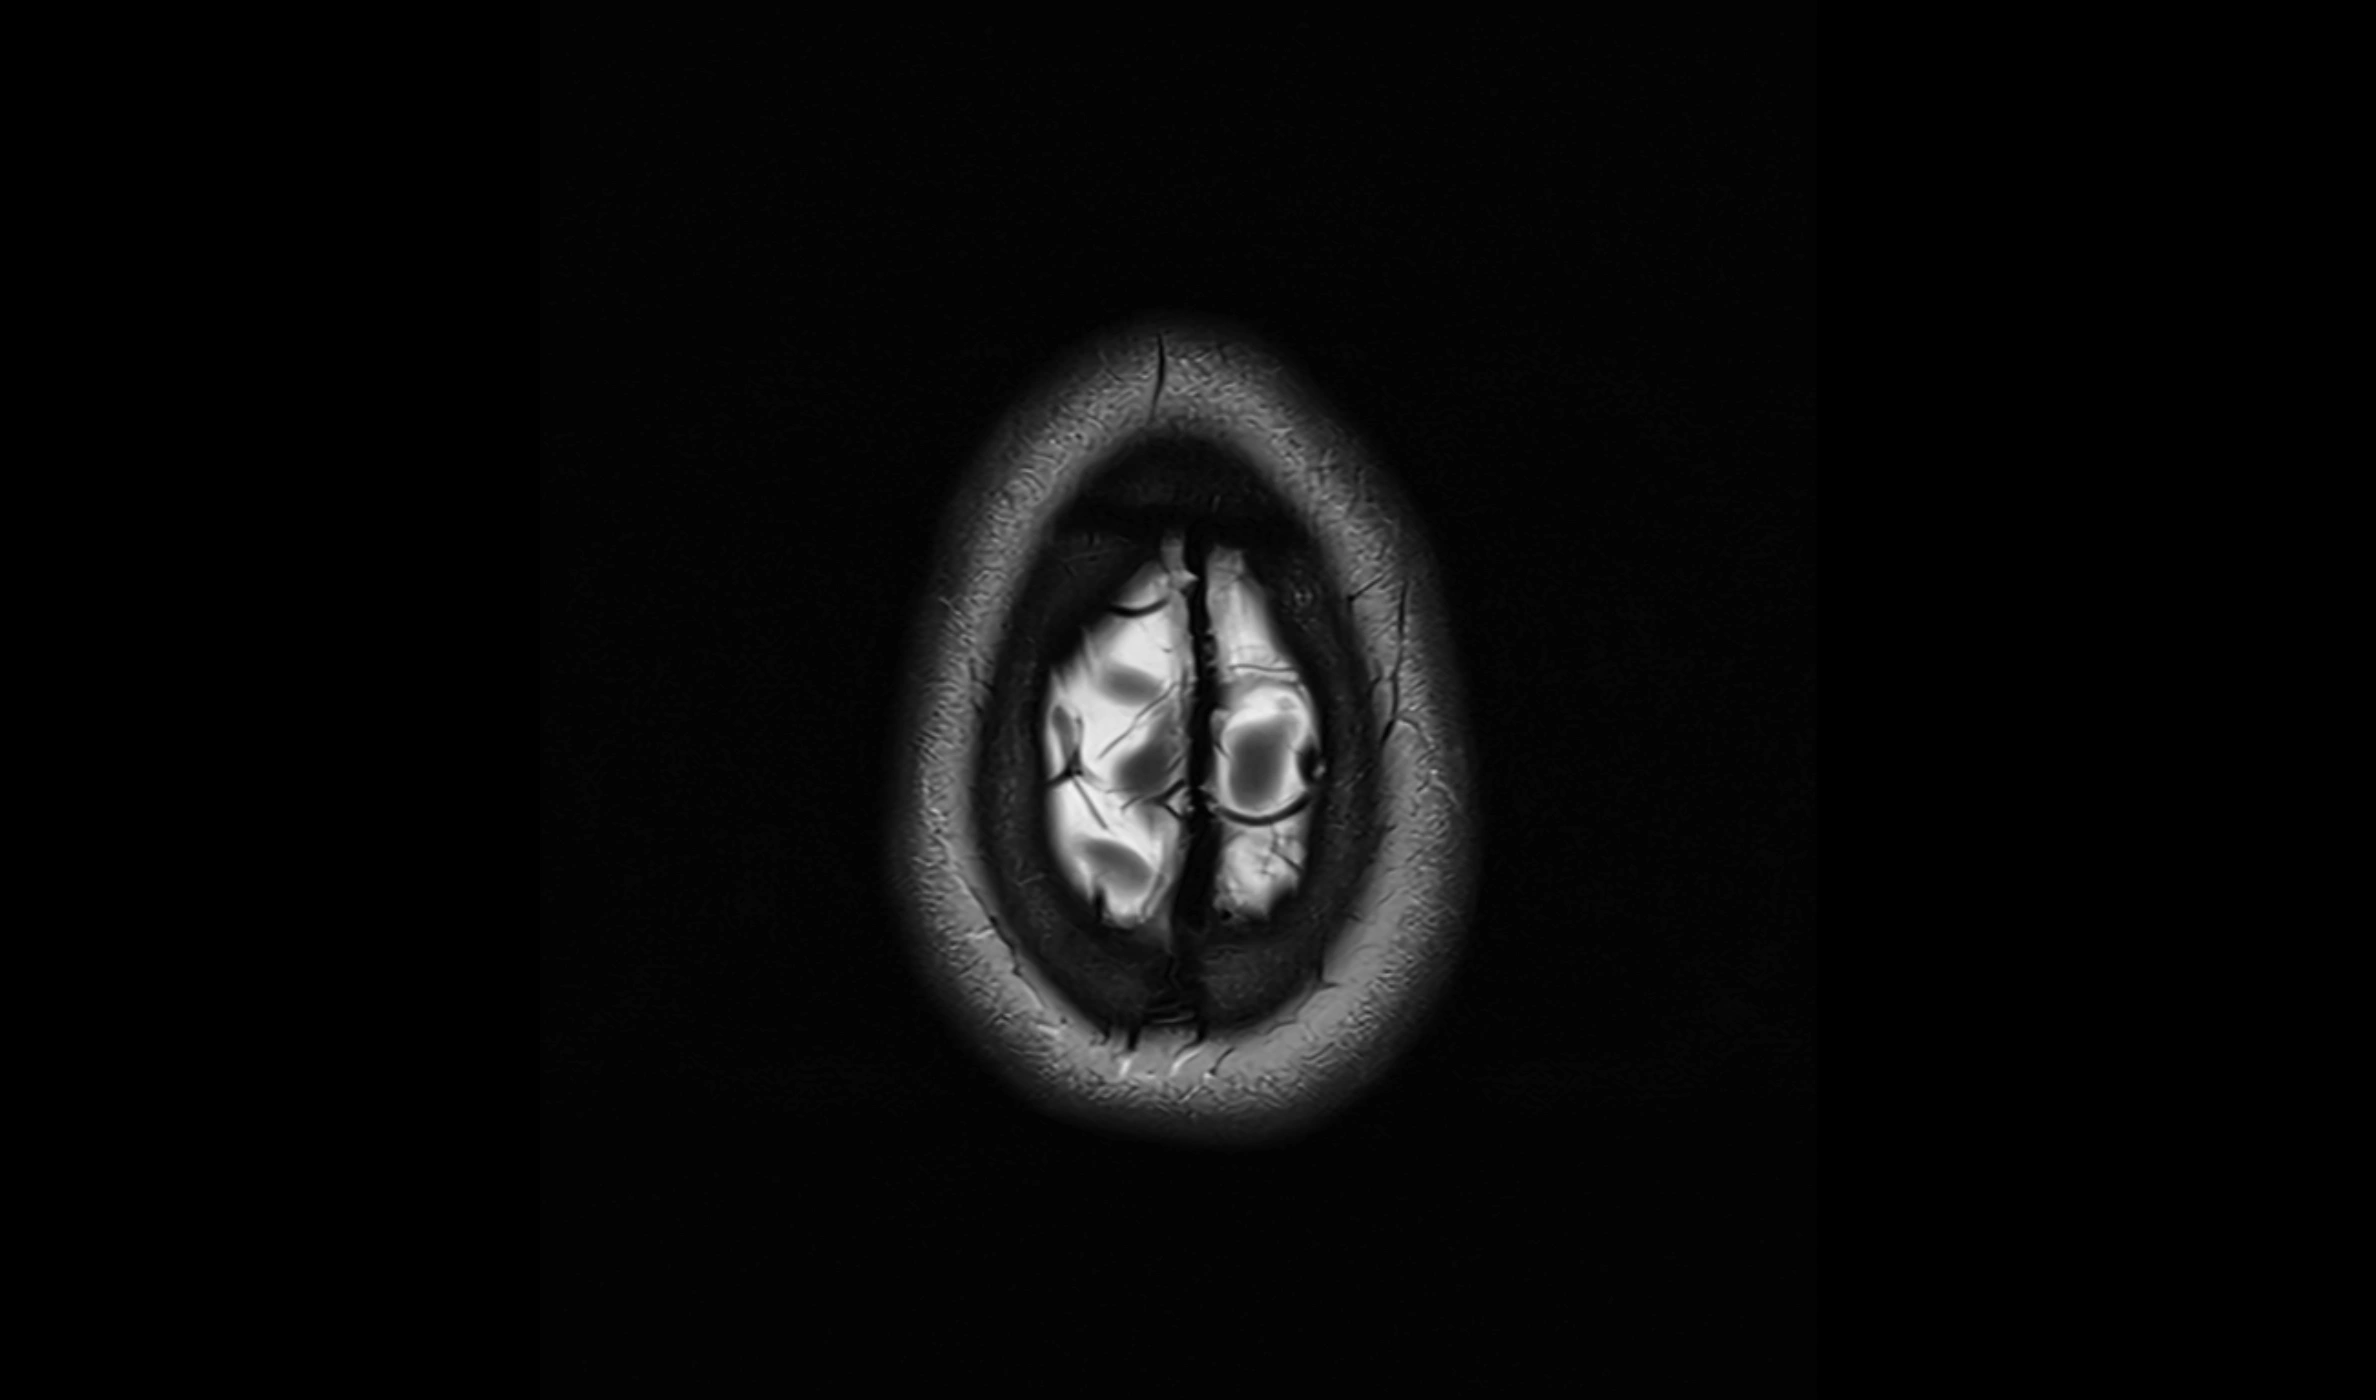

image